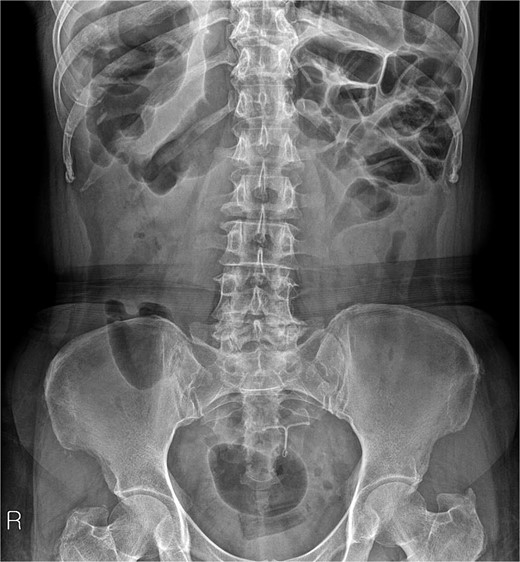

A 54-year-old woman, gravida 4, para 2, presented at the outpatient department with abnormal colonoscopy findings. She had a history of hypertension and underwent an IUD insertion for contraception one year after delivery in 2000. However, in 2007, when she visited the clinic for its removal, the IUD was not found on pelvic examination and ultrasound. The patient assumed that the IUD had been expelled spontaneously. Six months before her 2022 hospital visit, she experienced intermittent rectal bleeding and lower left abdominal pain, leading her to seek medical attention. Her medical history and physical examination, including a digital rectal examination, showed no notable abnormalities except for mild left lower quadrant tenderness. Routine laboratory investigations yielded unremarkable results. During colonoscopy, a foreign body was observed penetrating the sigmoid wall, surrounded by granulation tissue (Fig. 1). Subsequently, an abdominal simple X-ray and computed tomography scan were performed, revealing that the foreign body was an IUD, located next to the left side of uterus and entering the sigmoid colon (Figs 2 and 3).

IUD positioning adjacent to the left uterus and extending into the colon, observed on CT.